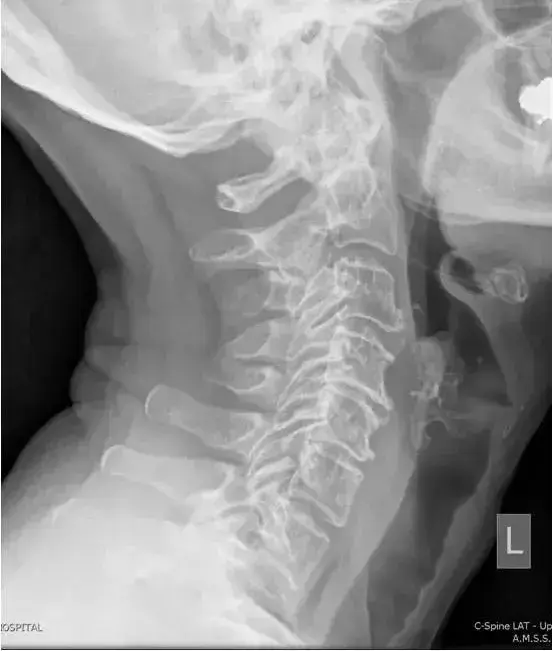

图7、颈椎侧位片,生理曲度返弓。

图10、颈椎侧位片,颈椎生理曲度后凸

图11:颈椎侧位。正常的颈椎对准。在C3-C4,C4-C5和C5-C6水平上注意到小的前部骨赘形成。C4-C5水平的椎间隙变窄,轻度终板硬化。还注意到C4-C5和C5-C6水平的关节肥大。

图12:颈椎侧位。颈椎生理曲度变直。椎体高度正常。在C4-C5和C5-C6水平存在椎间隙变窄,前骨赘形成。在相同水平注意到轻度钩椎关节肥大。C4-6椎体后缘没有对齐。

图13:颈椎侧位片。。轻度损失C4,C5和C6椎体的高度。在C4-C4和C5-C6水平上有大量的前部骨赘形成。C6-C7水平的高度损失非常轻微。